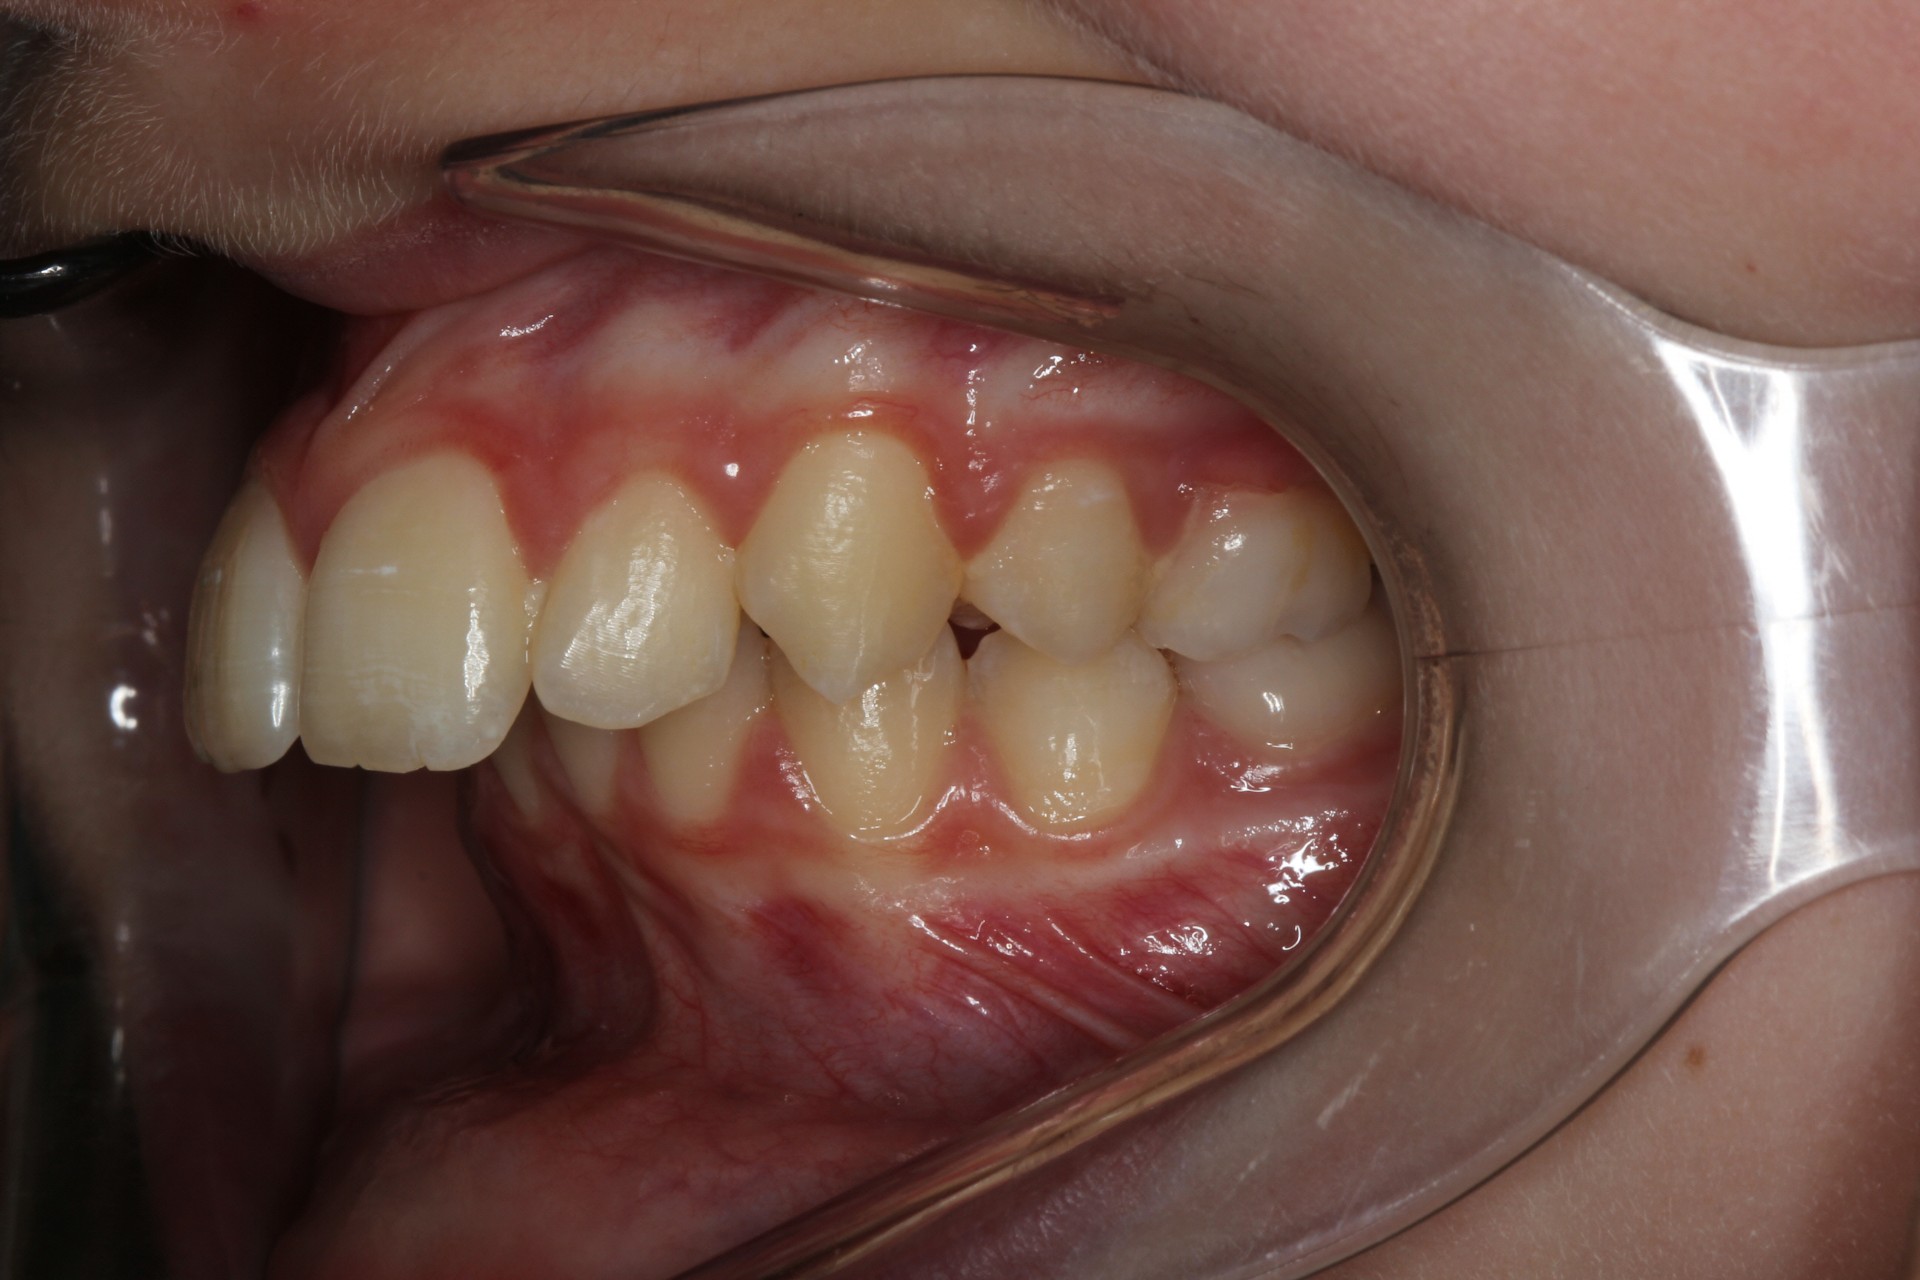

Protruding front teeth with midline diastema – Child case